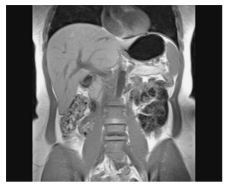

Assinale a alternativa que apresenta a

estrutura que NÃO pode ser visualizada na

imagem a seguir.